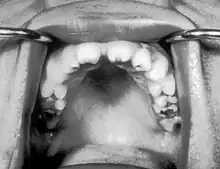

Notched incisors known as Hutchinson's teeth which are characteristic of congenital syphilis | |

- Blunted upper incisor teeth known as Hutchinson's teeth

A frequently-found group of symptoms is Hutchinson's triad, which consists of Hutchinson's teeth (notched incisors), keratitis and deafness and occurs in 63% of cases.[18]

- Hutchinson's triad, a set of symptoms consisting of deafness, Hutchinson's teeth (centrally notched, widely spaced peg-shaped upper central incisors), and interstitial keratitis (IK), an inflammation of the cornea which can lead to corneal scarring and potential blindness